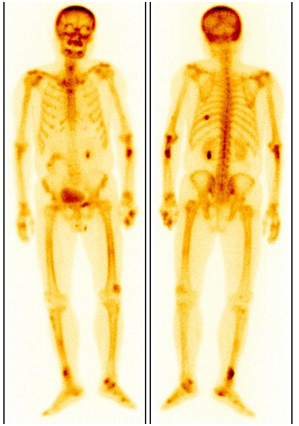

肺腺癌患者,左圖為2018年12月ECT,未見明顯異常;期間未復(fù)查;2023年5月骨痛來診,ECT顯示全身多發(fā)骨轉(zhuǎn)移(右圖)。